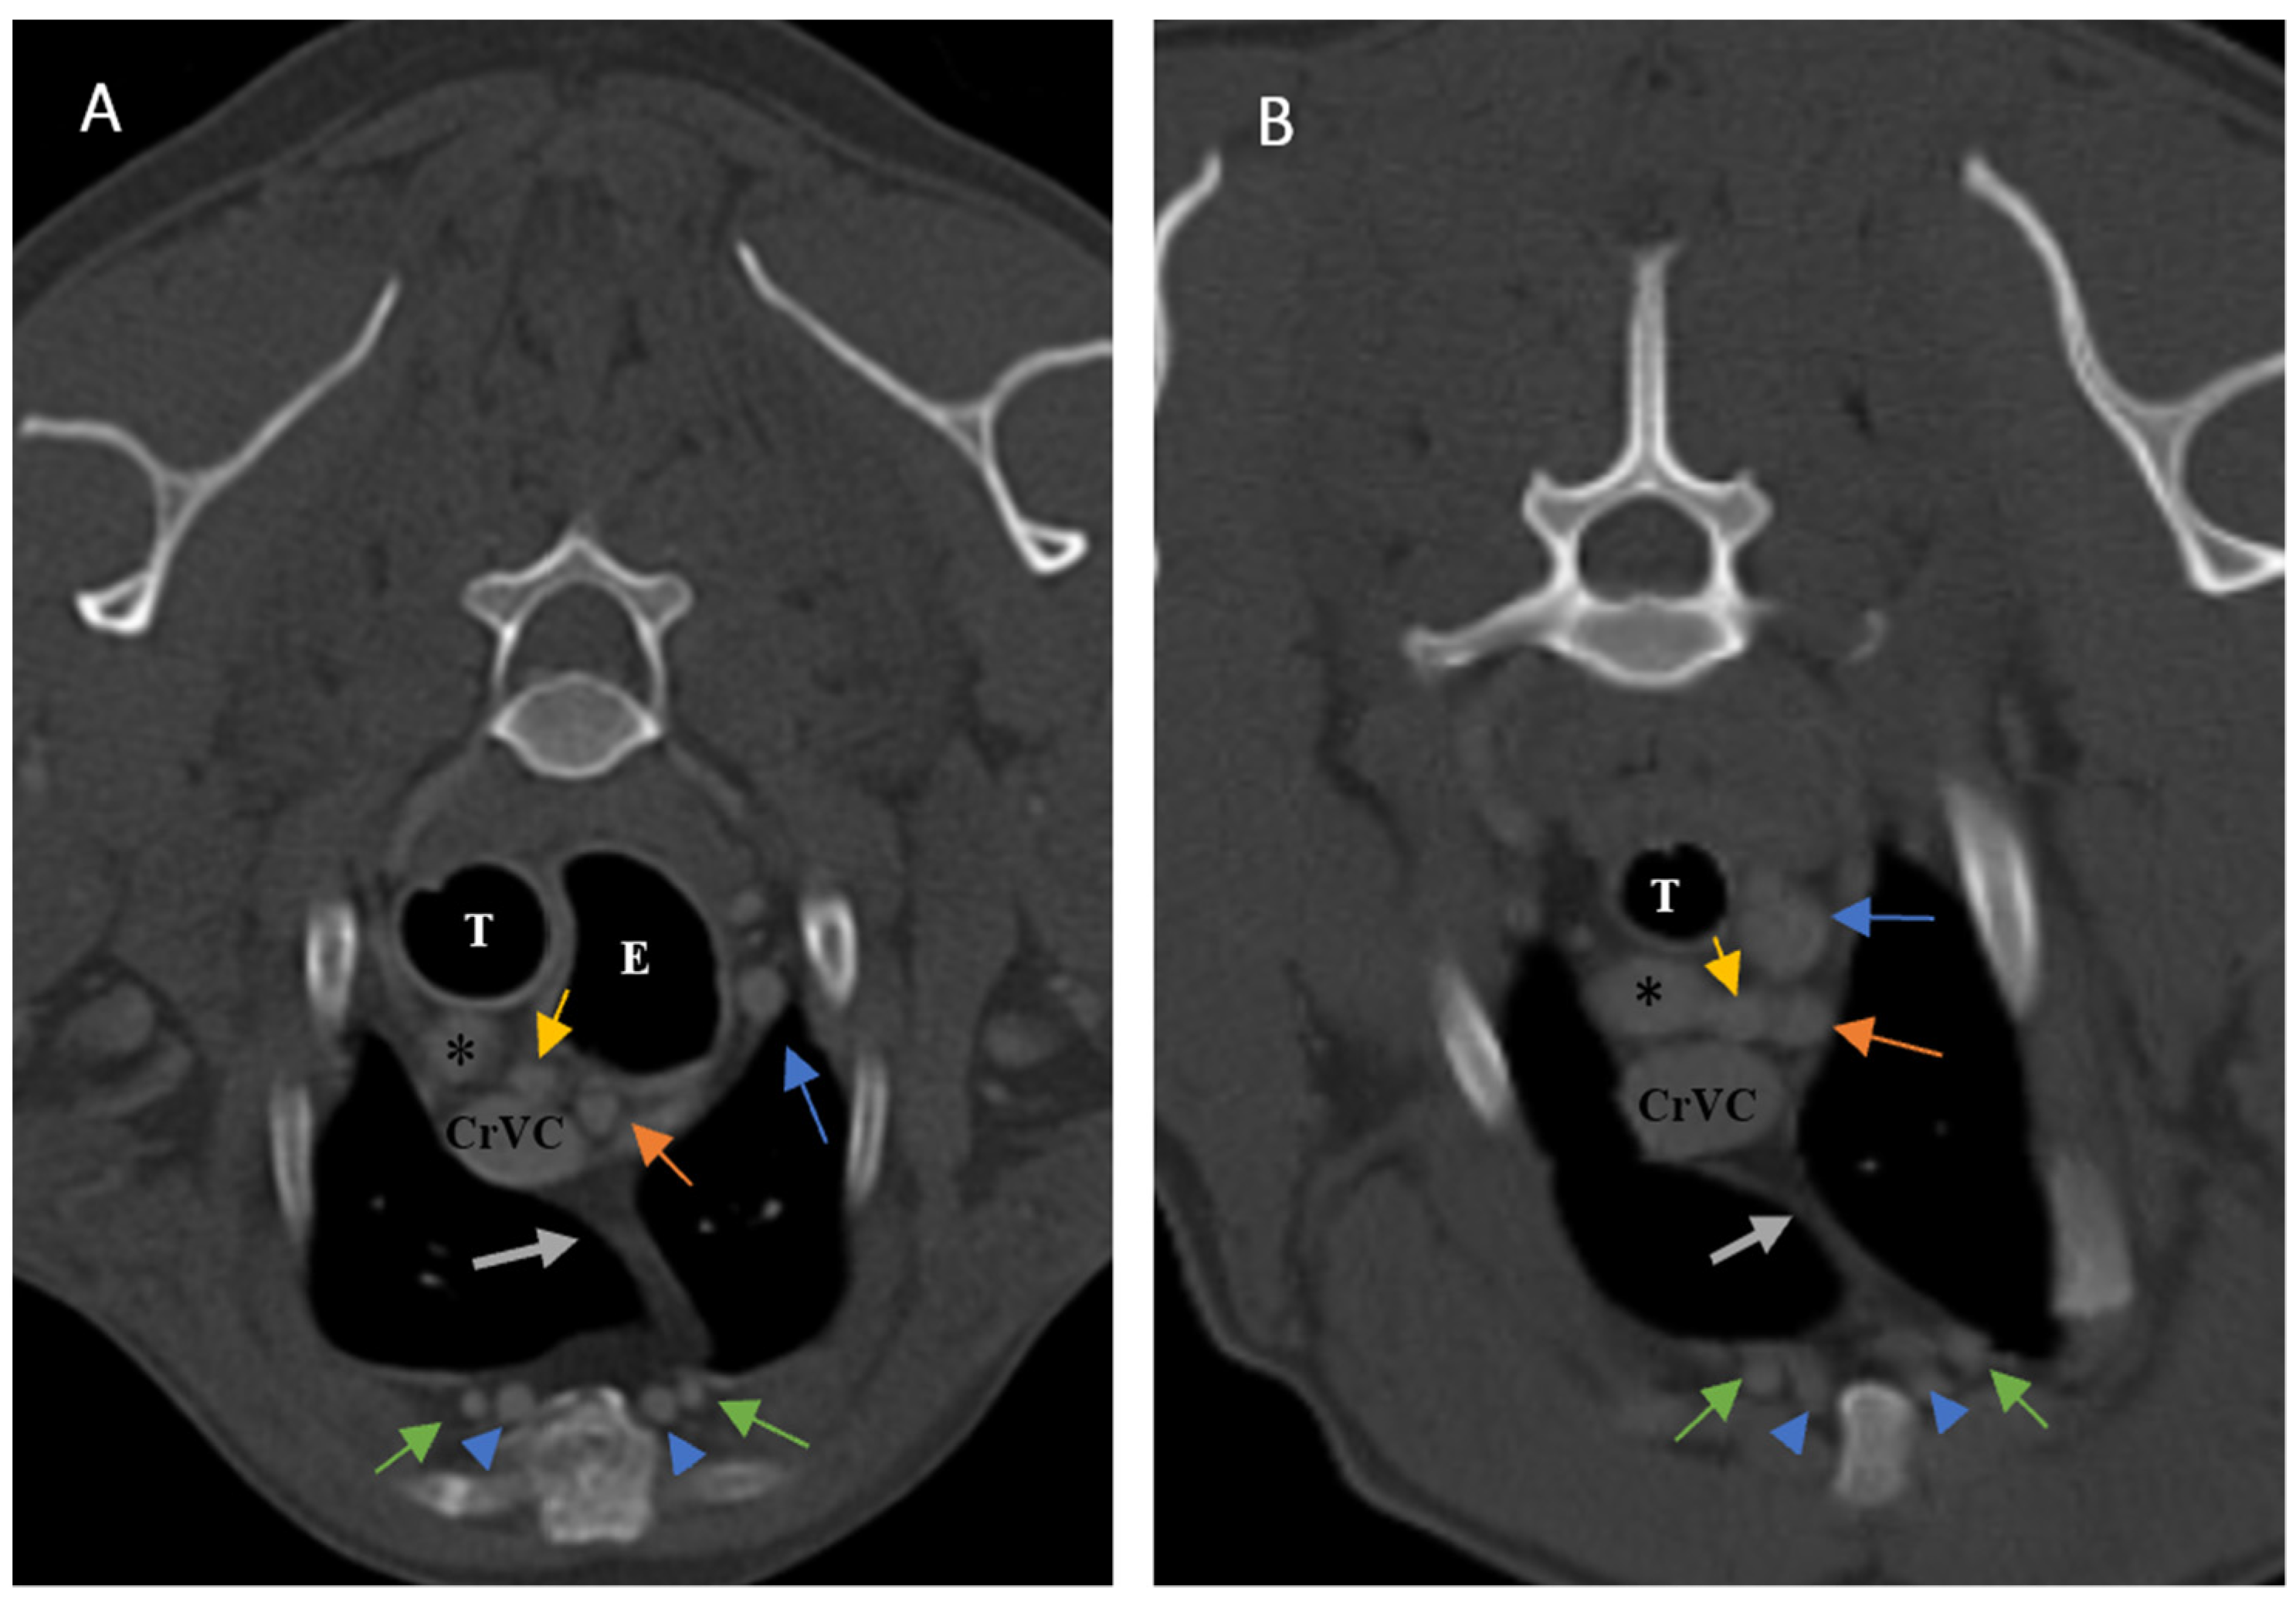

Figure 6. Illustration of visibility and topographic location of grade 1 thymus in contrast-enhanced transverse sections of the thoracic region at the level of T3 (A) and T4 (B). (A): Six-year-old female Terrier with a visible, grade 1, rectangular-shaped thymus with concave borders, left-sided predominancy and mottled appearance (CT number: −55). (B): Nine-year-old male terrier with a visible grade 1, rectangular-shaped thymus with concave borders, left sided predominancy and mottled appearance. Light grey dash lines show thymic borders. CrVC: cranial vena cava, grey arrow: right costocervical vein, blue arrow: left subclavian artery, yellow arrow: right common carotid artery, orange arrow: left common carotid artery, arrowheads: internal thoracic arteries and veins, black asterisk: right common carotid artery, and white asterisk: brachiocephalic trunk.